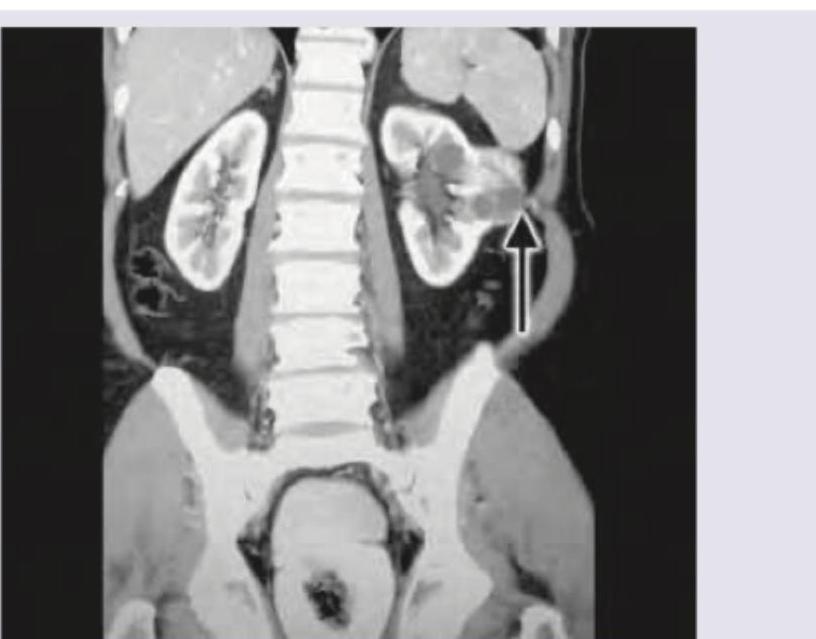

Explanation: ***Hydronephrosis*** - The MRI image clearly shows **dilatation of the renal pelvis and calyces** in the left kidney, indicated by the arrow. This uniform distension is characteristic of hydronephrosis secondary to obstruction. - This condition results from an **obstruction of urine outflow**, leading to urine accumulation and subsequent swelling of the kidney's collecting system. *RCC* - **Renal cell carcinoma (RCC)** typically presents as a solid mass or lesion within the kidney parenchyma, which is not depicted in this image. - While an RCC could cause obstruction leading to hydronephrosis, the primary finding here is fluid distension, not a solid tumor. *Nephronophthisis* - **Nephronophthisis** is a genetic disorder characterized by **cysts primarily in the renal medulla** and progressive renal failure. It typically causes small, shrunken kidneys with numerous small cysts, not widespread pelvicalyceal dilation. - It usually manifests in childhood or adolescence with symptoms related to chronic kidney disease, which doesn't directly correspond to the imaging finding of marked collecting system dilation. *Polycystic kidney* - **Polycystic kidney disease** is characterized by the presence of **multiple cysts of varying sizes throughout the renal parenchyma**, leading to enlarged, distorted kidneys. - The image shows a single, dilated collecting system rather than numerous discrete cysts distributed throughout the kidney.